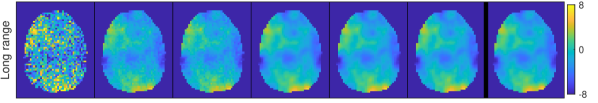

4.2.3 Prior simulation

To better understand the meaning of the different priors in practice, Fig. 4 displays samples from the spatial priors using the estimated hyperparameters for the first regressor of the different datasets. The M and ICAR priors produce fields that vary quite rapidly, while the second order priors give realizations that are more smooth. For the word object dataset we note that the short estimated range for M gives a sample with much faster variability than the sample from ICAR, which looks unrealistically smooth. This illustrates the problem with using the infinite range ICAR prior for a dataset where the inherent range is much shorter.